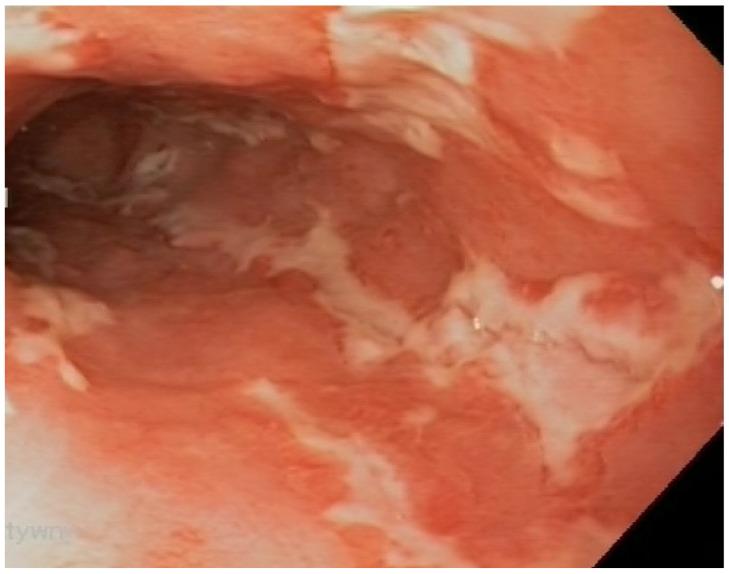

BACKGROUND/OBJECTIVES: Crohn's disease is known for being associated with an abnormal composition of the bacterial flora, dysbiosis and intestinal function disorders. Metabolites produced by gut microbiota play a pivotal role in the pathogenesis of CD, and the presence of unspecific extraintestinal manifestations.

背景/目的:克罗恩病以与细菌菌群组成异常、生态失调及肠道功能紊乱相关而闻名。肠道微生物群产生的代谢产物在克罗恩病的发病机制以及非特异性肠外表现的出现中起关键作用。